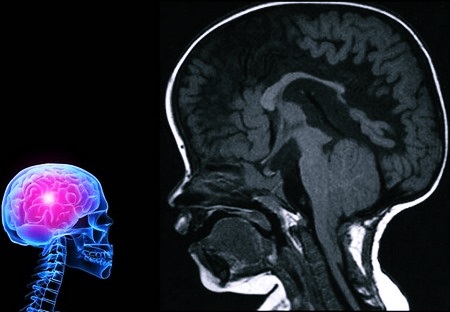

Врачи отмечают, что аномалия Арнольда-Киари представляет собой серьезное неврологическое заболевание, которое требует внимательного подхода к диагностике и лечению. Специалисты подчеркивают, что симптомы могут варьироваться от головной боли и головокружения до более серьезных неврологических нарушений. Важно, чтобы пациенты, у которых есть подозрение на данное заболевание, проходили полное обследование, включая МРТ, для точной диагностики.

В связи с этим в последнее время наиболее часто применяется МРТ (магнитно-резонансная томография) – единственный простой и достоверный способ диагностики данной аномалии развития головного и спинного мозга. Поскольку для ее проведения необходима полная обездвиженность человека, то для обследования маленьких детей вводят в состояние так называемого медикаментозного сна.